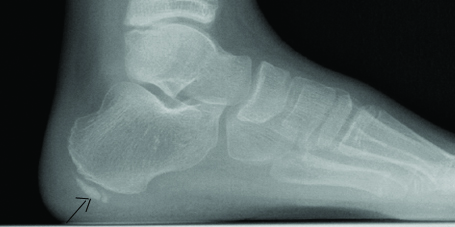

The physical examination at the final presentation to the hospital revealed a calendar age of 13 years 1 month, height 141 cm (-2.06 SDS) body weight 28.4 kg (-2.62 SDS), weight according to height 81%, and testis volumes of 5/5. There was pain in both heels increasing with palpation but with no increase in temperature, hyperaemia or swelling. He could not put his weight on his heels when walking. Laboratory tests revealed haemoglobin 13.4 gm/dL, leukocytes 5420/μL, and thrombocytes 218.000/μL with no atypical cells in the peripheral smear. The lateral foot graph revealed a sclerotic and fragmented apophysis [Table/Fig-1,2]. The patients GH treatment was continued, and he was recommended bed rest and in case of excessive pain the patient was advised nonsteroidal anti-inflammatory drugs. Follow up was undertaken jointly with the Department of Orthopaedics. After three months of follow up the pain in both heels and limping was regressed.

Fragmentation appearance of calcaneal apophysis on lateral foot graph.